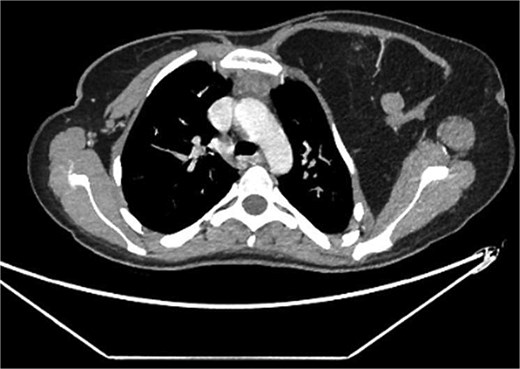

A 22-year-old female presented with progressive swelling in the left anterior chest wall above the left breast, associated with needle-like chest pain, left upper limb tingling, and weakness. The patient had a history of childhood cystic hygroma in the left axilla, previously excised. She denied constitutional symptoms but reported compressive symptoms such as shortness of breath, dysphagia, and hoarseness. A family history of breast cancer with thyroid metastasis was noted in her mother. On examination, the patient exhibited multiple bilateral solitary thyroid nodules and a bulky swelling in the left anterior chest and axilla. Computed tomography (CT) imaging (Fig. 1) revealed hypodense bilateral thyroid nodules, with magnetic resonance imaging (MRI) (Fig. 2) showing an enhancing left axillary lesion (2 cm, previously 1 cm) and an anterior chest wall lesion (1 cm). The mass, measuring 23 × 8 cm, extended to the lower left neck, left chest wall, and left axilla, encasing the neurovascular bundle without muscle or osseous invasion (Fig. 3). Fine-needle aspiration (FNA) cytology (Fig. 4) of the right thyroid nodule indicated atypia of undetermined significance (Bethesda III), while left-sided nodules and biopsies from the axilla, breast, and neck confirmed benign mature adipose tissue. The patient underwent total thyroidectomy, level V left neck exploration, and excision of lipomatous masses from the axilla, anterior chest, and breast, involving multiple surgical teams. Intraoperatively, vocal cords were preserved, and clear planes for lipoma excision were identified. The total excised lipomatous tissue weighed 13.57 kg (Fig. 5). Pathological examination confirmed mature adipose proliferation with no malignancy. Fluorescence in situ hybridization (FISH) ruled out MDM2 amplification, and genetic testing returned negative. Postoperatively, the patient developed deep vein thrombosis (DVT) in the left upper limb, diagnosed via Doppler study, and was treated with low-molecular-weight heparin (LMWH) followed by rivaroxaban. Follow-up MRI at 2 days and 3 months confirmed no residual or recurrent tissue growth. The patient started levothyroxine for thyroid function management and monitored for optimal dosing.

Left chest wall lipomatosis with extension to the left neck and left axilla with thin septations, and there is a small enhancing focus (within the fatty lesion) which could be a small enhancing nodule or lymph node. The overall measurement has relatively increased (consider patient maturation).